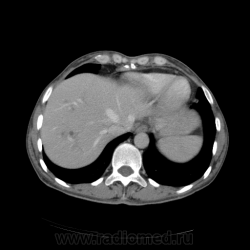

КТ ОБП - гепатомегалия, признаки панкреатита

МРТ ОБП - от 16.12.10 гепатомегалия, расширение панкреатических протоков.

Похоже на то, что все было списано на калькулезный холецистит. Наши морфологи пересмотрели стекла с гистологией и окончательно написали о наличие высокодефференцированной аденокарциноме. У меня только две мысли образования исходит из БДС или первичный рак 12п.к., хотя сейчас гадать бесполезно. 12п.к. циркулярно сужена.